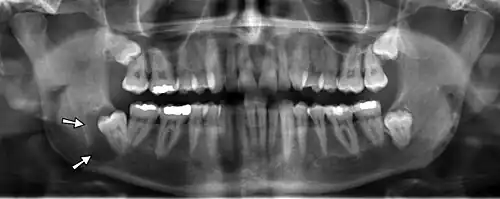

Radiograficamente, o cisto dentígero se apresenta como uma lesão radiolúcida bem delimitada unilocular, frequentemente com uma borda radiopaca esclerótica, ao redor da coroa de um dente incluso.[1][6] Suspeita-se de um cisto dentígero quando o espaço do folículo dentário é maior que 5 mm.[1]

Possui algumas variantes radiográficas:[7]

- Central: a mais comum, em que o cisto circunda a coroa do dente, partindo da junção amelocementária;

- Lateral: geralmente associada a terceiros molares inferiores mesioangulados parcialmente erupcionados, o cisto se desenvolve lateralmente à raiz e circunda parte da coroa;

- Circunferencial: o cisto recobre a coroa e se estende rumo à raiz, dando a impressão de que o dente emerge do cisto.